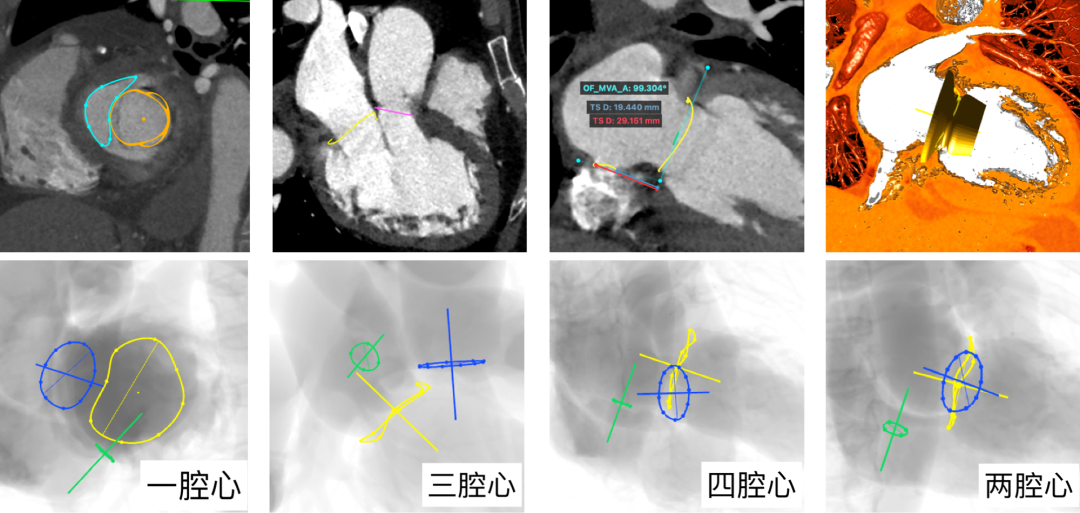

术前,宋光远教授带领团队与Nicolo Piazza教授、Jean Buithieu教授充分进行技术探讨与交流,基于详细的CT测量分析,判断评估患者术中风险并规划手术策略。

通过CT影像进行全时相二尖瓣瓣环径线测量、房间隔穿刺高度预估、各腔心投照角度选择,并模拟植入Peijia HighLife TSMVR瓣膜,预判人工瓣膜与毗邻组织贴靠良好且无左室流出道梗阻风险。该例患者瓣下腱索结构相对友好,对于导丝成环过程干扰较小,而患者左心房结构较小,预估房间隔穿刺位点较低(仅约3cm),瓣膜释放时空间相对受限,需额外注意。